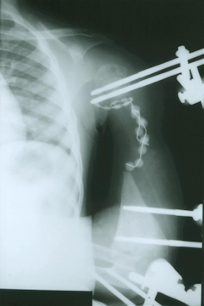

Diagnose: Entzündung linker Oberarm mit Verlust des Oberarmknochens

Therapie: Transplantation des Wadenbeins als Ersatz des Oberarmknochens mit mikrovaskulärer Anastomisierung zur Wiederherstellung der Funktion des Armes